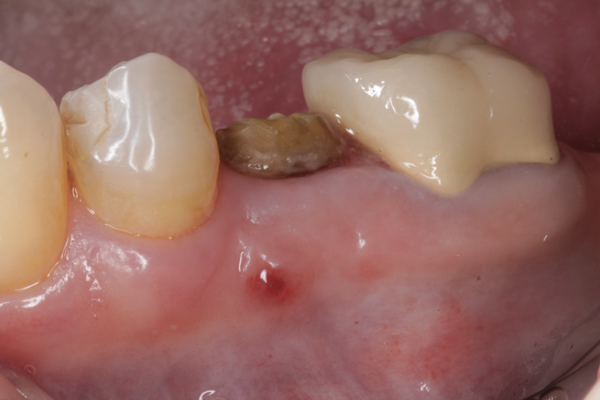

Fig 23. Implant inserted in a regenerated ridge after 6 months healing.

Figure 23

Fig 24. Cone beam scan demonstrating bone circumferentially around the dental implant.

Figure 24

Fig 25. Radiograph showing appearance of restored implant after 1 year.

Figure 25